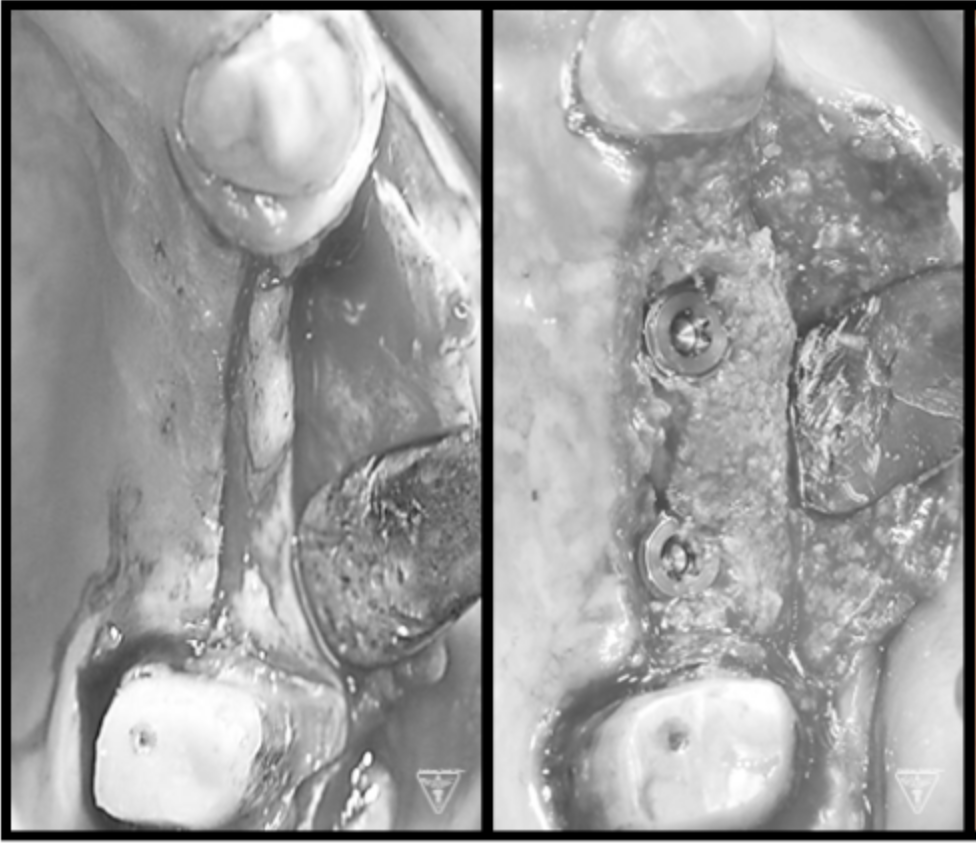

骨再生治療

インプラント